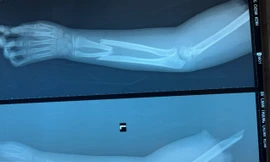

TPO - Trong lúc lao động, ông Nguyễn Trí Đức bị máy cuốn đứt lìa cánh tay, Bệnh viện Đa khoa khu vực Long Khánh, tỉnh Đồng Nai đã phẫu thuật nối thành công cánh tay cho bệnh nhân.

TPO - Do có dấu hiệu của bệnh trầm cảm và dùng thuốc kích thích nên nam thanh niên đã tự chặt đứt cánh tay của mình trong nhà tắm. Khi nghe tiếng la từ nhà tắm, mẹ anh Ngọc chạy vào thì tá hỏa chứng kiến cánh tay của con trai đã bị đứt lìa.

TPO - Đến bây giờ, ít người biết đến câu chuyện sơ cứu ban đầu cho cháu Ngọc Bích (tám tuổi), nạn nhân duy nhất sống sót trong vụ thảm sát, cướp tiệm vàng Ngọc Bích ở Bắc Giang sáng 24 - 8, cũng như việc hướng dẫn người nhà bảo quản cánh tay cháu để các y, bác sĩ nối lại thành công.